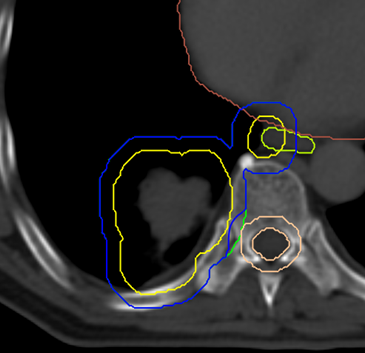

Case : Locally advanced non-small cell lung cancer

Dose Prescription:

95% PGTV 60.2 Gy/2.15 Gy/28 F

95% PTV 50.4 Gy/1.8 Gy/28 F

Protocol : RTOG0617

Techniques : IMRT/VMAT/HT